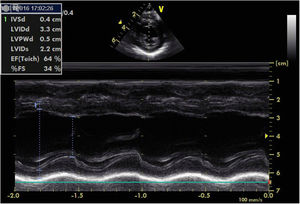

For the next six months, BP remained stable with no need to initiate new drugs, and echocardiographic progress was favorable, with gradual improvement of left ventricular function. At 10 months of age, the patient underwent right nephrectomy without complications. Since then, gradual weaning from the drugs was possible. At 11 months of age, recovery of ventricular function was confirmed (LVEF 64%, LVSF 34%); the patient continued to have a very slightly dilated left ventricle (Figure 4).